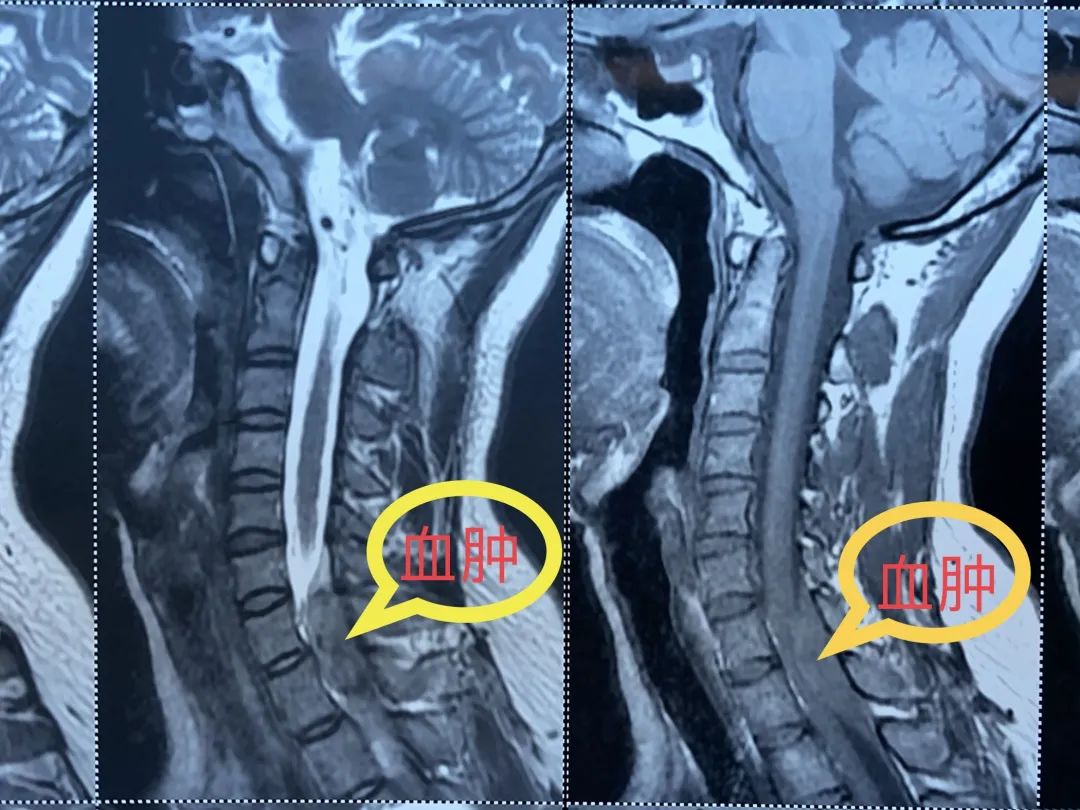

医生为患者申请紧急核磁检查,结果显示:颈髓有一个巨大的肿物压迫着。

小真的核磁片子

随后,小真被转到了神经外科治疗,经神经外科医生判断,小真的情况是颈椎管内急性出血导致的,而不正确的扭动脖子和推拿按摩很可能是主要原因。